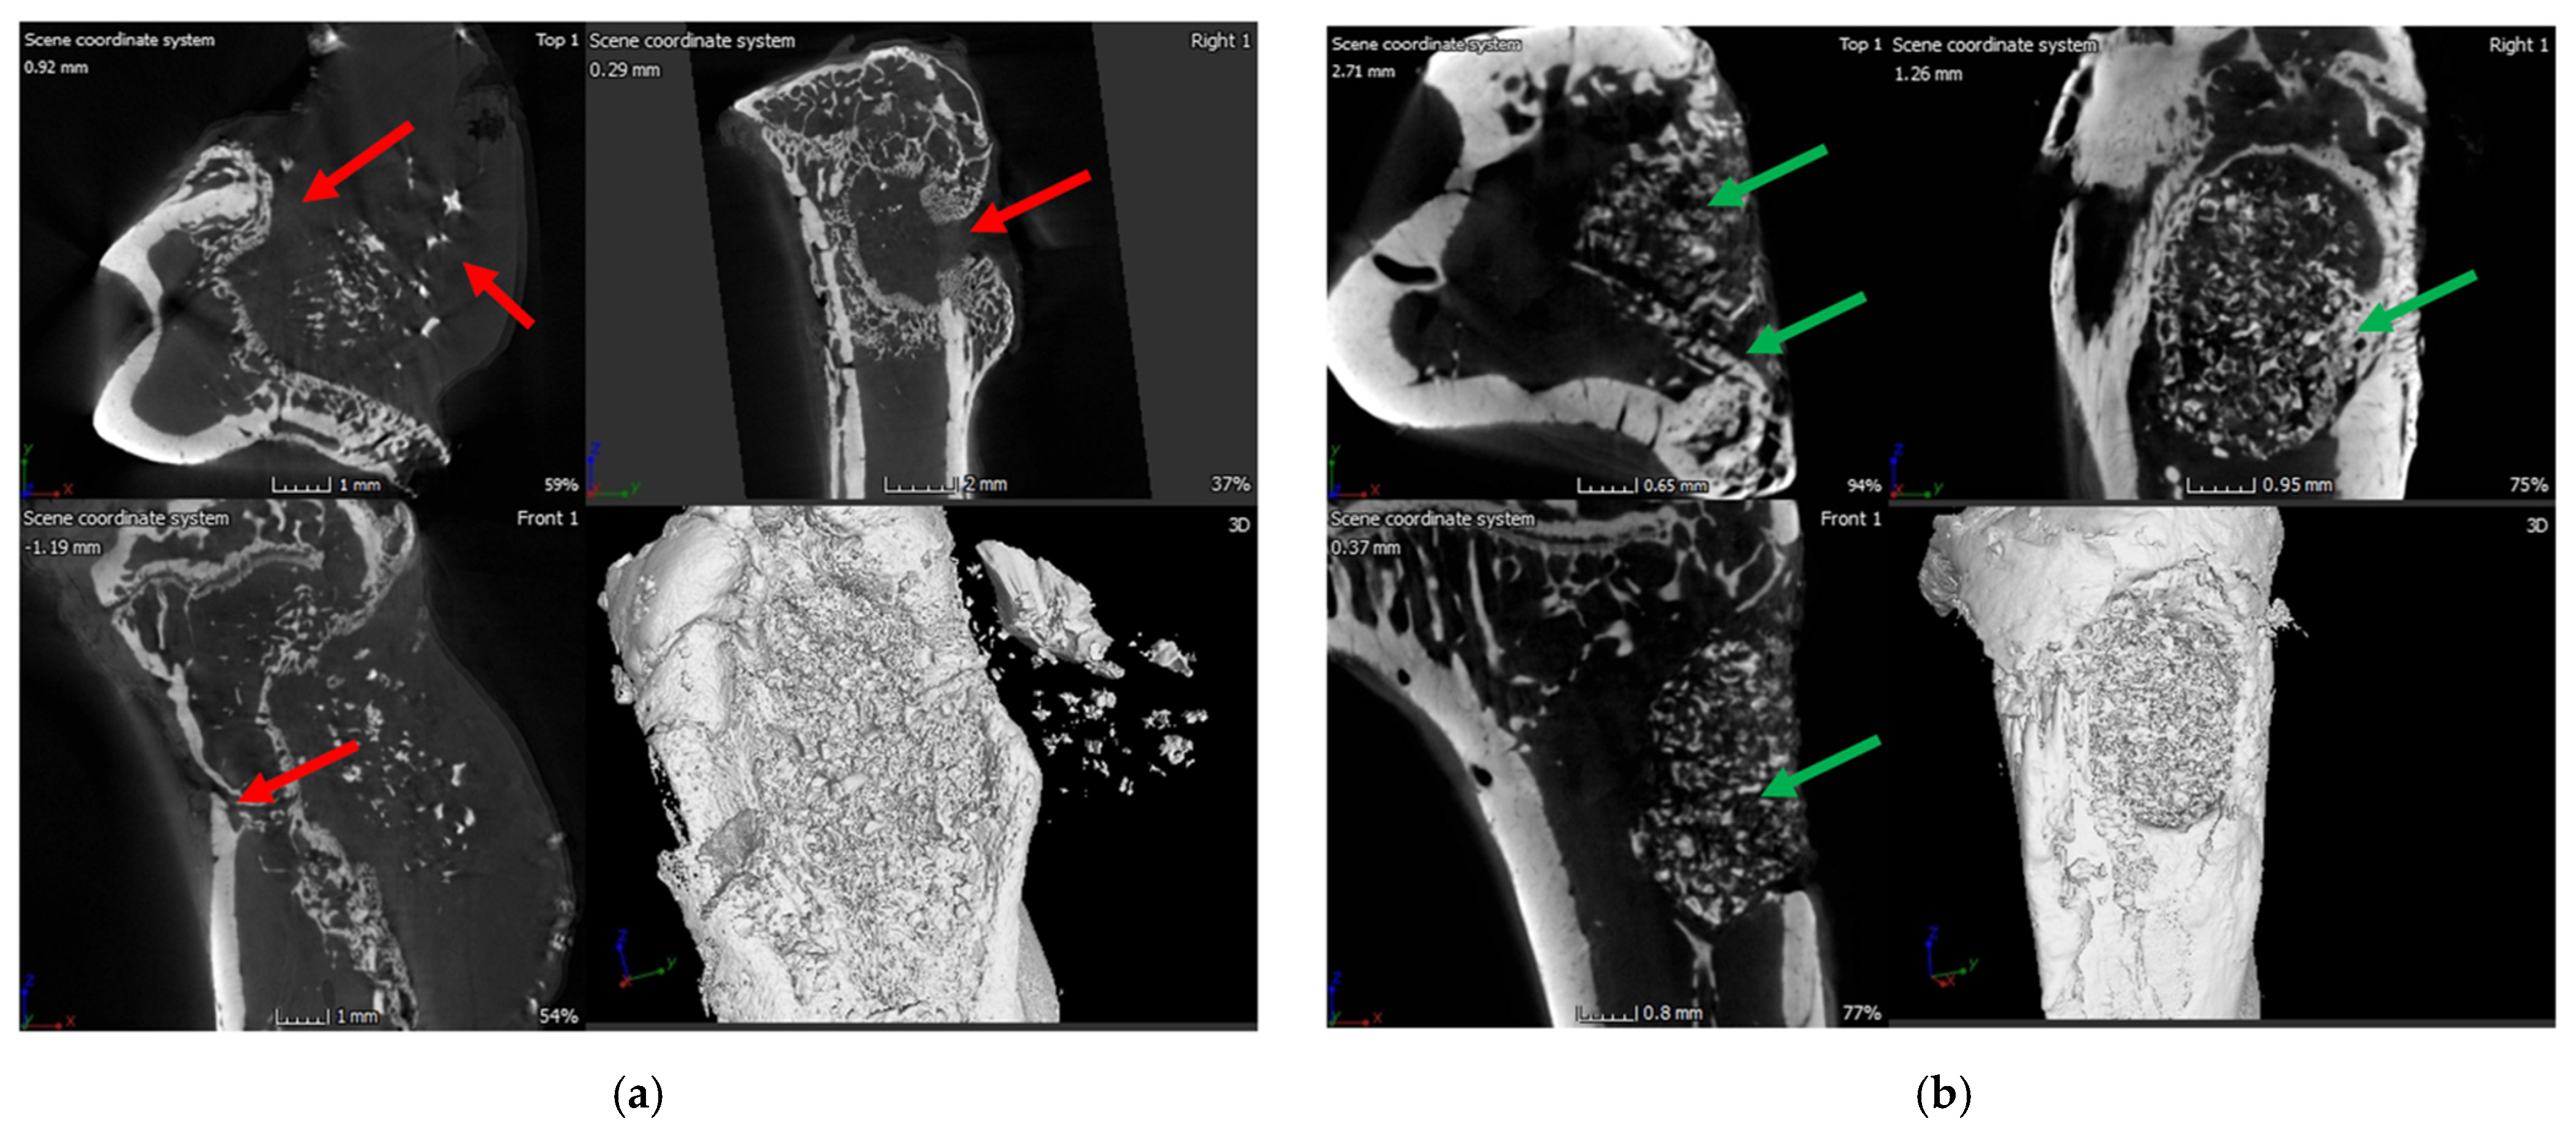

2.6.1. X-ray and μ-CT of Rat Bones

4.7.2. X-ray and μ-CT of Rat Bones